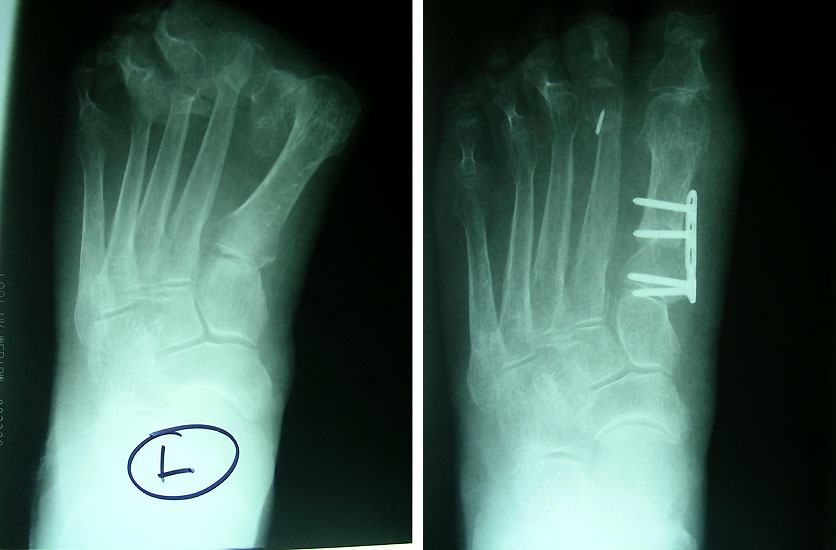

• Röntgenaufnahmen des Fußes in 2 Ebenen stehend (d.p., seitlich).

Zum Lesen der Bildbeschreibung und Vollansicht bitte die Bilder anklicken.

• Röntgenkontrolle am ersten postoperativen Tag sowie nach 3 und 6 Wochen.

Die basisnahe Crescentic Osteotomie gehört zu den Standardeingriffen zur Korrektur fortgeschrittener Hallux valgus Fehlstellungen. Ein distaler Weichteileingriff sollte routinemäßig mit durchgeführt werden. Die Mobilität des ersten Strahls wird auf ein normales Maß reduziert und ermöglicht wieder eine normale Lastaufnahme 1. Der Intermetatarsale Winkel wird gut korrigiert. Die Verwendung einer winkelstabilen Plattenosteosynthese zur Fixation einer proximalen Osteotomie am MT I hat sich bereits bewährt894. Häufig wird additiv eine Akin Osteotomie durchgeführt. Irritationen über der tastbaren Platte führen in vielen Fällen zur Metallentfernung.